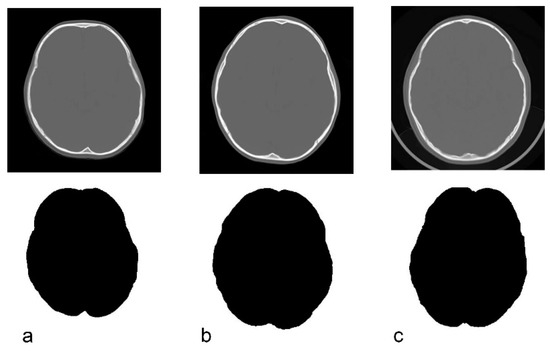

2.3. Image Processing Method for CT Data